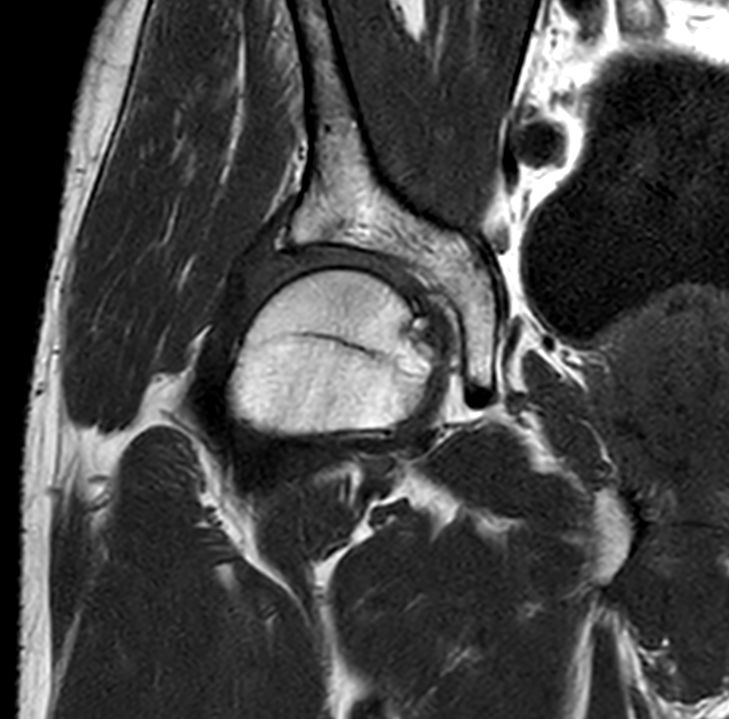

Sagittal T2w TSE

Sagittal T2w TSESmartSpeed

Sagittal T2w TSESmartSpeed Resolution